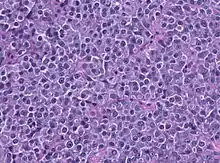

Description de l'image PRL HE histology.jpg.

Le prolactinome est une tumeur bénigne (adénome) de l'hypophyse (sécrétant de la prolactine). Il en résulte un excès de prolactine qui peut être ajusté par exemple par la bromocriptine (agoniste de la dopamine). Il apparaît surtout chez les jeunes femmes[1].